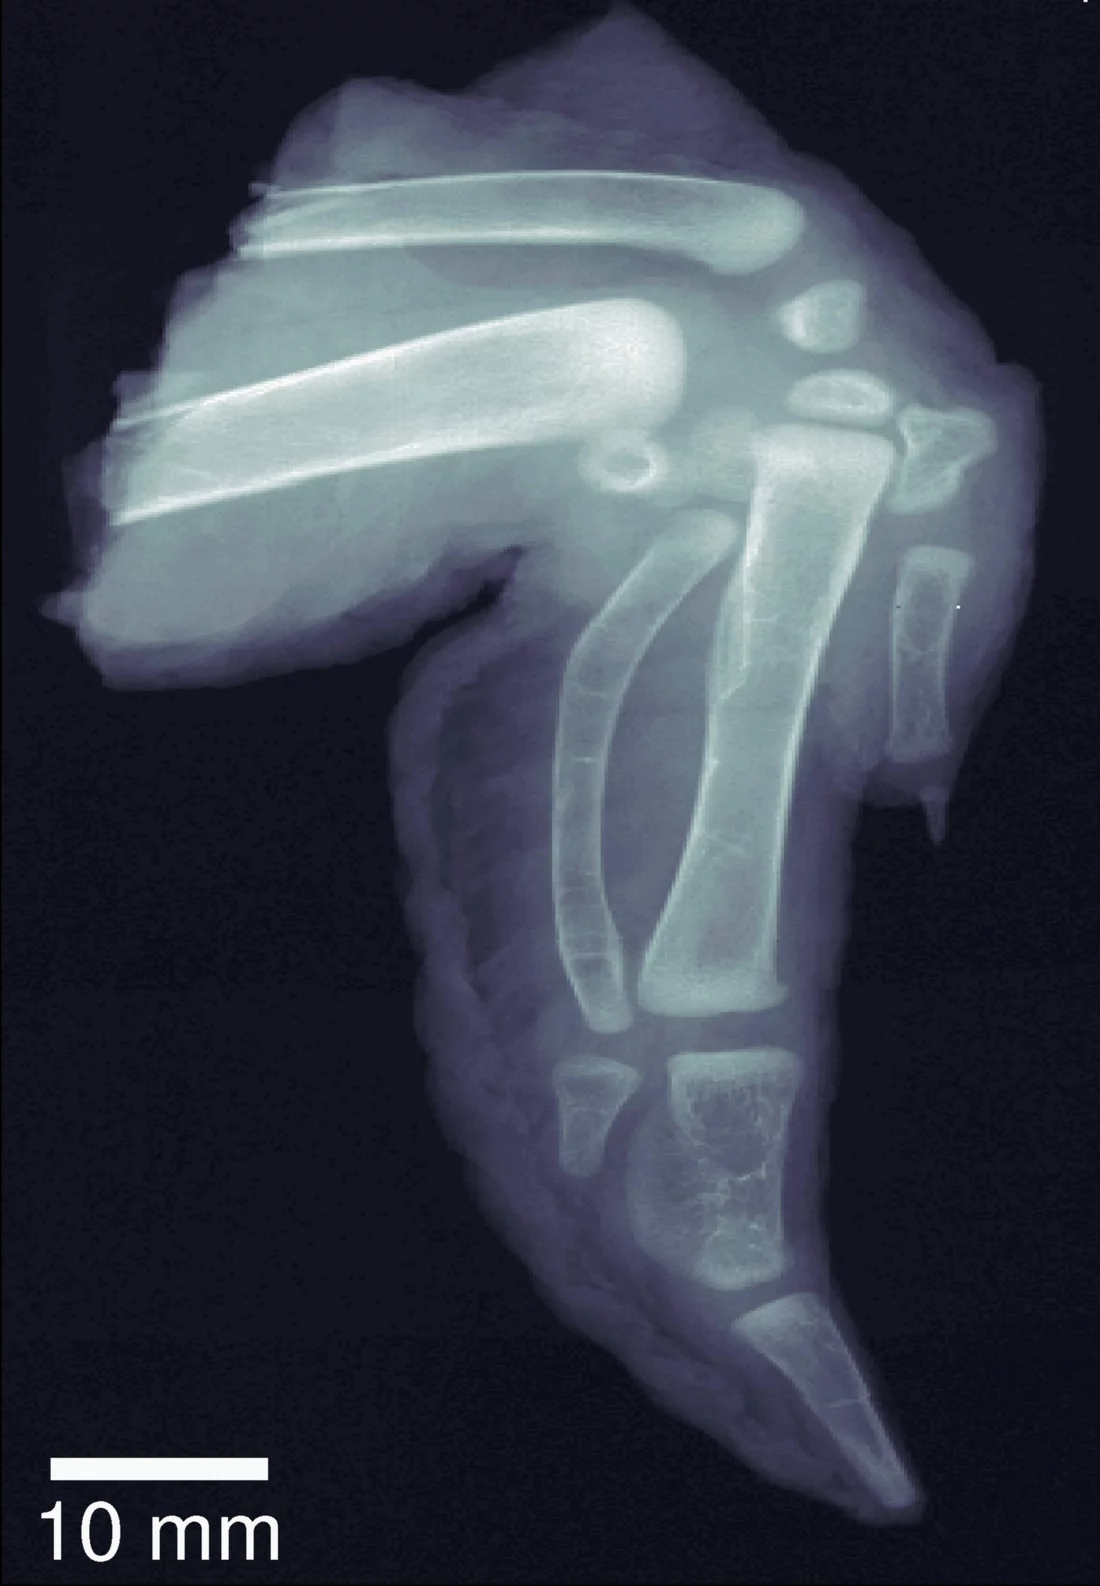

Herkömmliches Röntgenbild eines Hühnerflügels.

Mehr Details sind auf einem Dunkelfeld-Röntgenbild zu sehen.

Im Gegensatz zur herkömmlichen Röntgentechnik, bei der nur die Kontrastunterschiede angezeigt werden, berücksichtigen Dunkelfeld-Röntgenbilder die Streuungseigenschaften im Inneren von Werkstoffen. Auf diese Weise können vor allem Weichgewebe besser analysiert werden und bereits geringe Strukturveränderungen bei Knochen oder Legierungen werden erkennbar. Dies erlaubt bestimmte Krankheiten wie Brustkrebs oder Alzheimer frühzeitiger und zuverlässiger zu diagnostizieren. Die Methode erleichtert auch die Diagnose von Osteoporose, da die Porosität und winzige Brüche des Knochens im Gegensatz zu den unscharfen herkömmlichen Bildern eindeutig erkennbar sind. Bei Sprengstoffen werden Röntgenstrahlen aufgrund ihrer Mikrokristallstruktur stark gestreut. Dank der neuen Methode können sie auch bei traditionellen Sicherheitsanlagen leichter erkannt werden. Da dieses neue Verfahren die Werkstoffe nicht verändert, fördert es auch winzige Risse und Roststellen in Strukturen wie beispielsweise Flugzeugflügeln oder Schiffsrümpfen zutage.